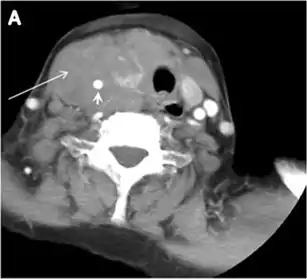

Intra-thyroid parathyroid adenoma

Parathyroid adenoma (PA) is the most common cause of primary hyperparathyroidism. Ectopic parathyroid adenoma is rare. The third and fourth pharyngeal pouches represent the embryological origin of the parathyroid tissues, and ectopic parathyroid adenoma can ultimately develop anywhere along their migration course. In a large retrospective study of patients with primary hyperparathyroidism, PA was detected in the intra-thyroid location in 0.7% of cases. In another retrospective analysis of 202 patients with ectopic PA, the intra-thyroidal location was found in 18% of the cases. Intra-thyroid parathyroid adenomas mimic thyroid nodules in CT scans and may even show uptake on a thyroid iodine scan. Correlation with laboratory workup, including measurement of serum parathyroid hormone and calcium level, is required. In addition, the evaluating radiologist should search for radiological manifestations of hyperparathyroidism, such as osteopenia, bone resorption, and brown tumours (Fig. 22).[1]

Fig. 22. A 26-year-old male patient with elevated serum parathyroid hormones and calcium secondary to intra-thyroid parathyroid adenoma. a, b Enhanced axial and coronal CT scan of the neck demonstrate a well-defined hypodense right thyroid nodule (white arrows). c Bone window coronal CT scan shows lytic expansile lesions at the right mandible and left frontal bone (white arrows). d Transverse colour Doppler ultrasound of the neck demonstrates a well-defined, heterogonous, predominantly hypoechoic right thyroid nodule measuring 2.7 cm, with mild increased vascularity and no internal micro-calcifications (white arrow). e, f Delayed anterior planar and fused SPECT/CT parathyroid Sestamibi scan at 2 hours demonstrate persistent focal activity in the right thyroid lobe (white arrows). Note the scattered mandibular/maxillary uptakes in planar image representing the known brown tumours.[1]

In the case of inconclusive Tc99m Sestamibi and neck US imaging, FNA biopsy with FNA-iPTH (intact parathyroid hormone) measurement can provide simultaneous biochemical and cytological evidence. Elevated FNA-iPTH measurement, as compared to serum iPTH, is considered positive and diagnostic of parathyroid adenoma.[1]